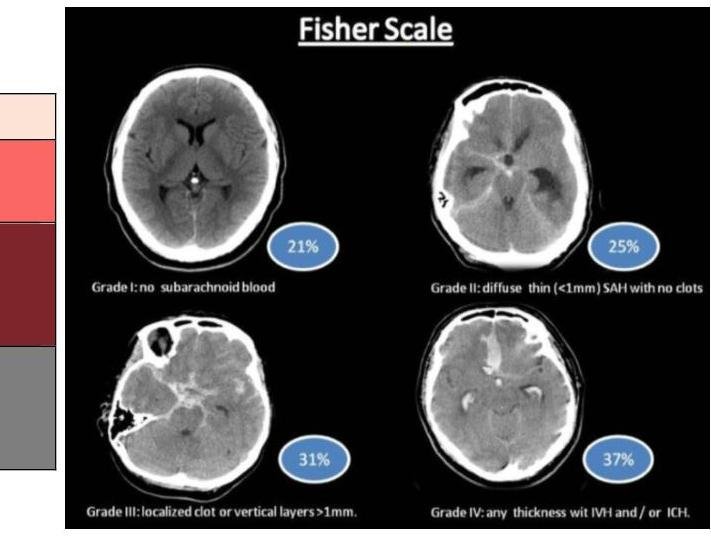

# EVC HEMORRÁGICO ## DEFINICIÓN Tal como se ha planteado en el documento de EVC Isquémico, estos eventos corresponden a un síndrome clínico caracterizado por el **rápido desarrollo de síntomas y signos correspondientes a un déficit neurológico focal** y que persisten por más de 24 horas, sin otra causa aparente distinta a la de origen vascular, que además se visualiza por estudios de imagen.  El EVC de origen hemorrágico corresponde aproximadamente al 20% de todos los EVC que se presentan, siendo la causa más frecuente la **hemorragia subaracnoidea**, secundaria a un traumatismo, aunque también puede presentarse secundaria a una ruptura aneurismática, con menor frecuencia. ## LOCALIZACIÓN ## Ganglionar 48 % ## Tálamo 23 % ## Lobar 15 % Puente 6% ## Cerebelo 5% Núcleo Caudado 3% ## Etiología | Hipertensión Arterial | Ganglios basales, tálamo, lobar, puente, cerebelo | | :--: | :-- | | Malformaciones vasculares | Cerebelo, intraventricular, lobar, puente, subaracnoidea | | Aneurismas Cerebrales | **HEMORRAGIA SUBARACNOIDEA** (no provocan hemorragia parenquimatosa) | | Angiopatía Amiloide | (debilidad de los vasos, se degenera la íntima media) - lobar, subaracnoidea | | Coagulopatías | Lobar, subaracnoidea, cerebelo | | Tumores | Depende de localización | | Fármacos y drogas | Lobar, subaracnoidea, intraventricular | # EPIDEMIOLOGÍA FACTORES MODIFICABLES - HAS - DM - Tabaquismo y alcoholismo - Cardiopatías congestivas - Valvulopatías, FA, IAM - Dislipidemia - Sedentarismo y obesidad - Traumatismos - Aneurismas - Malformaciones Arteriovenosas - Angiopatía Amiloide - Anticoagulantes. ## FACTORES DE RIESGO PARA ANEURISMA - Edad: 40-65 años $\rightarrow$ 80 % - Femenino 3:2 Masculino - HTA - Tabaco - Alcohol-Cocaína ## FACTORES NO MODIFICABLES - Edad avanzada - Género masculino - Historia familiar de EVC # HEMORRAGIA SUBARACNOIDEA Ocurre cuando la **RUPTURA VASCULAR** se extravasa **HACIA EL ESPACIO SUBARACNOIDEO** - La sangre se disemina hacia las cisternas basales y el espacio subaracnoideo ## ETIOLOGÍA 1. **ANEURISMAS SACULARES** (70-85%) que tienen forma de saco. Defectos congénitos de pared muscular y elásticas de arterias o adquiridos a través de cambios degenerativos de pared arterial. **Fuerza de rozamiento** (Stress) hemodinámico y herencia se han implicado en el desarrollo o ruptura del aneurisma. 2. MAVs - pueden reventarse subaracnoidea, pero habitualmente son parenquimatosas. 3. TCE 4. Otros: disecciones, micóticos  ## CLÍNICA - Es de inicio **ABRUPTO** con una **CEFALEA INTENSÍSIMA**. - DESCRITA COMO **LA PEOR DE SU VIDA**. - Seguida de rigidez nucal o signos meníngeos - Fotofobia, náuseas, vómitos - Parálisis de nervios craneales y déficit motor Hemorragia Subhialoideas Ya que el nervio óptico es una expansión del SNC.  (c) Copyright 2021-2022 Joyas ENARM - Todos los derechos reservados - # DIAGNÓSTICO ## GOLD STANDARD: Angiografía Cerebral Selectiva con Sustracción Digital - Permite identificar el aneurisma y al ser este la causa más frecuente será el ideal. ## 1ra elección: TOMOGRAFÍA COMPUTARIZADA - Es el estudio más indicado por la accesibilidad - Si la tomografía es negativa y tiene datos de aneurisma, lo más probable es que solamente haya goteado. - Se sugieren los otros estudios para vigilancia. ## RESONANCIA MAGNÉTICA - Es el estudio de elección, pero en caso de no contar con ella se utiliza TAC ## PUNCIÓN LUMBAR - Si la Tomografía Computarizada resulta negativa, ante la sospecha se debe realizar **PUNCIÓN LUMBAR**. ## ESCALAS AUXILIARES Estas escalas solamente aplican para casos en los que la hemorragia es subaracnoidea y exclusivamente provocada por rupturas aneurismáticas. ## ESCALA DE FISHER I Sin evidencia de sangrado en cisternas ni ventrículos II - **SANGRE DIFUSA** fina - Capa **MENOR 1 mm** en cisternas medida verticalmente - **COÁGULO** grueso cisternal III - Su tamaño es **MAYOR 1 mm** en cisternas medida verticalmente IV $\cdot$ **HEMATOMA INTRAPARENQUIMATOSO** - Hemorragia Intraventricular - Puede o no haber sangrado difuso  ESCALA DE HUNT Y HESS | $\mathbf{1}$ | Paciente asintomático, dolor de cabeza leve, ligera rigidez de la nuca | | :-- | :-- | | $\mathbf{2}$ | Dolor de cabeza moderado - fuerte, rigidez de la nuca, sin déficit neurológico fuera de la parálisis del nervio craneal | | $\mathbf{3}$ | Somnolencia, confusión, obnubilación, déficit neurológico focal leve. | | $\mathbf{4}$ | Estupor, hemiparesia moderada - severa, rigidez de descerebración temprana | | $\mathbf{5}$ | Coma profundo, signos de descerebración. | # TRATAMIENTO ## PREVENIR RESANGRADO - Será importante durante las primeras 48 horas. - Mantener TA Sistólica por debajo de 150 mmHg hasta realizar clipaje o embolización PREVENIR VASOESPASMO (la complicación más grave) Y DETERIORO NEUROLÓGICO Esto puede ocurrir a los 5-7 días. Administrar BLOQUEADORES CANALES DE CALCIO IV: - 1ra elección **NIMODIPINO** (Estrictamente por SNG 2 tabletas cada 4 horas) - El nimodipino IV está contraindicado porque aumenta la mortalidad ya que genera hipotensión sanguínea que puede condicionar una falla en la autorregulación. - Otros: Amlodipino, Nifedipino, Verapamilo - Soluciones IV ## DISMINUIR PRESIÓN INTRACRANEAL - Mantener posición semi-Fowler - Tratar la hidrocefalia con ventriculostomía ## TRATAMIENTO DEFINITIVO - OCLUSIÓN VASCULAR O QUIRÚRGICA CON CLIP  # HEMORRAGIA INTRAPARENQUIMATOSA Son las hemorragias que se producen dentro del encéfalo como consecuencia de la ruptura de un vaso profundo, ya sea arterial o venoso. - La parenquimatosa no aneurismática - Es mayor en asiáticos, es intermedia en negros y es menor en caucásicos - MEXICO mayor que USA en 20% - 26 % de los EVC Las más graves son las **HEMORRAGIAS DEL CEREBELO**, rápidamente crece el hematoma y comprime ## Factores de riesgo: - **HIPERTENSIÓN ARTERIAL** - La más importante - Condición predisponente más importante - Factor de riesgo modificable - El control de la HTA reduce el riesgo de HC en 50% - El cambio primario es el daño a la capa media de la pared del vaso. - Alcohol - Induce hipertensión esencial primaria - Bebedores ligeros hasta 414 ml / mes - Bebedores moderados hasta 1.2 L/mes - Bebedores intensos mayor a 1.2 L /mes - Colesterol - La dislipidemia es un factor de riesgo. Disminuir los lípidos. - En Hemorragia cerebral si te pasas, puedes favorecer - Debilitar el endotelio favoreciendo el desarrollo de hemorragia - **MENOR a 160 mg / dL** - Ácido Acetilsalicílico # CLÍNICA ## CEFALEA - 50% de los casos - Distorsión y tracción de meninges y vasos sanguíneos - Aumento generalizado de la PIC - Irrupción sanguínea a los ventrículos o al espacio subaracnoideo - Los hematomas pequeños puramente parenquimatosos no suelen producir cefalea. ## ALTERACIÓN DEL ESTADO DE ALERTA - Se asocia con la extensión y localización - El estado de coma fue más frecuente con hemorragia pontina - El estado de conciencia al ingreso es un factor pronóstico. Excepto en hemorragia **TALÁMICA**. - Todo lo que lesione el **TÁLAMO CAUSARÁ HIPERSOMNIA**. ## VÓMITO - Útil en el dx diferencial entre infarto y hemorragia - En el infarto 2% y hemorragia 48% ## CONVULSIONES - 6-15% ## DIAGNÓSTICO ## ESTUDIO DE ELECCIÓN: TOMOGRAFÍA COMPUTARIZADA - En la etapa aguda es el estudio de mayor sensibilidad - En la etapa subaguda y crónica es menos preciso | Etapa Hiperaguda ( 0-4 horas) | Lesión hiperdensa de color blanco | | :--: | :-- | | Etapa Aguda (5-72 horas) | Lesión hiperdensa (blanca) con mínimo contorno hipodenso (de color negro) | | Etapa Subaguda (4-21 días) | Lesión hiperdensa con máximo contorno hipodenso (que puede captar el contraste) | | Etapa Crónica (+21 días) | Lesión Isodensa (color gris) | # TRATAMIENTO - CONTROL DE TA: Labetalol e Hidralazina - Asistencia Ventilatoria - Posición Semi-Fowler - Intervención Qx si presenta efecto de masa. ## AUTORREGULACIÓN CEREBRAL - Capacidad de mantener la perfusión del cerebro, vasodilatando o vasoconstriñendo. - PAM +120 pierden la autorregulación - Las cerebrales posteriores prácticamente no tienen - Las cerebrales medias y anteriores se regulan  Hematoma Intraparenquimatoso Intracerebral # Hemorragias Intracraneales Hemorragia intraparenquimatosa Ruptura súbita de arteria intracerebral ## Etiología - HTA en < 55 años - Angiopatía amiloidea en > 55 años HTA es el principal factor de riesgo Hematoma epidural Lesión de la meníngea media por trauma Hay pérdida transitoria de memoria que se recupera para volver a sufrir deterioro del estado de alerta (lucidez intermedia) Clínica derivada de herniación uncal Toma forma biconvexa Hemorragia subaracnoidea Puede ser traumática o espontánea Frecuentemente por aneurismas Factores de riesgo - Tabaquismo (mujeres) - Alcoholismo - HTA Pueden presentar cefalea, náusea, vómito, **sx** meníngeo Hematoma subdural Ruptura de venas puente entre cerebro y senos durales Etiología traumática Toma forma de media luna